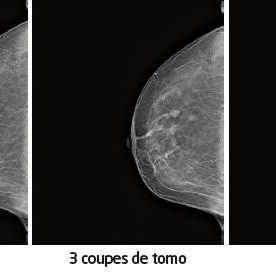

QUIZZ IMAGE 184

Proposé par le Dr Joël CRÉQUAT – Échographiste, Centre Péreire, Paris Contexte clinique Il s’agit de l’échographie d’un utérus en coupe sagittale.Le myomètre est homogène.L’endomètre est visible.On y observe 3 images rondes hyperéchogènes de quelques millimètres de diamètre.Qu’en pensez-vous ? Quelles hypothèses évoquez-vous ? Réponse : Il s’agit d’un DIU chinois, inconnu en…